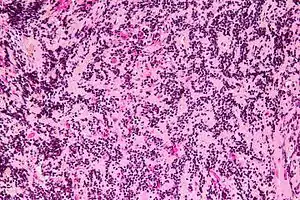

Micrograph of a pineocytoma. HPS stain.

Pineocytomas are diagnosed from tissue, i.e. a brain biopsy.They consist of:

• cytologically benign cells (with nuclei of uniform size, regular nuclear membranes, and light chromatin) and,

• have the characteristic pineocytomatous/neurocytic rosettes, which is an irregular circular/flower-like arrangement of cells with a large meshwork of fibers (neuropil) at the centre.[1] Pineocytomatous/neurocytic rosettes are superficially similar to Homer Wright rosettes; however, they differ from Homer Wright rosettes as they have (1) more neuropil at centre of the rosette and, (2) the edge of neuropil meshwork irregular/undulating.